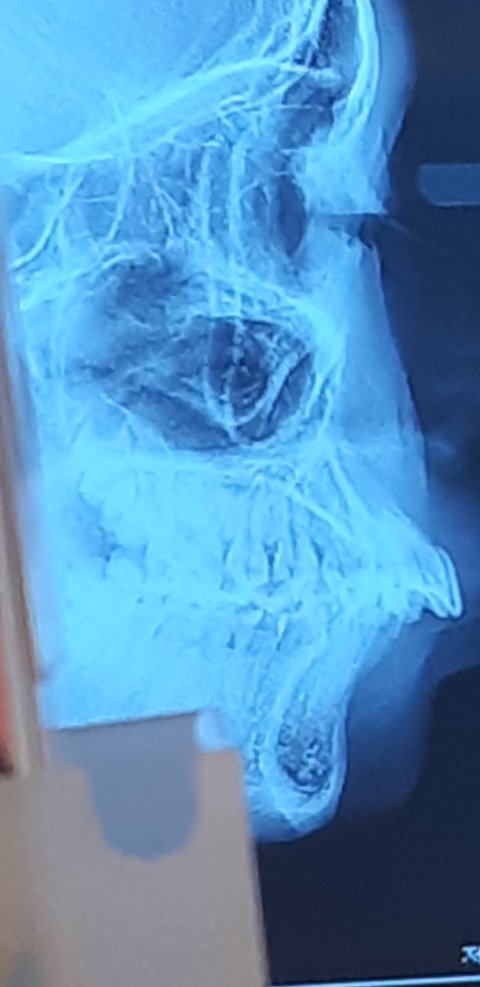

돌출입 심하나요..

교정 할까 여...